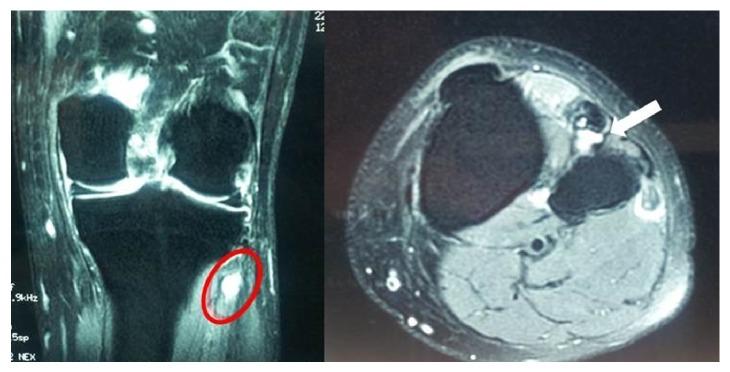

Lower extremities peripheral neuropathies caused by ganglion cysts are rare. The most frequent location of occurrence is the common peroneal nerve and its branches, at the level of the fibular neck. We report the case of a 57-year-old patient admitted with foot drop, due to an extraneural ganglion of the upper tibiofibular syndesmosis, compressing the deep branch of the peroneal nerve. Although there have been many previous reports of intraneural ganglion involvement with the lower limb nerves, to our knowledge, this is the second reported occurrence of an extraneural ganglion distinctly localized to the upper tibiofibular syndesmosis and palsying deep peroneal nerve. The diagnosis was made preoperatively using MRI. The common peroneal nerve and its branches were recognized and traced to its bifurcation during the operation, and the ganglion cyst was removed. Two months after surgery, the patient was pain-free and asymptomatic except for cutaneous anesthesia in the distribution of the deep peroneal nerve.

由腱鞘囊肿引起的下肢周围神经病变较为罕见。最常见的发病部位是腓总神经及其分支,位于腓骨小头水平。我们报告一例57岁患者,因上胫腓联合处的神经外腱鞘囊肿压迫腓深神经而出现足下垂入院。尽管此前已有许多关于神经内腱鞘囊肿累及下肢神经的报道,但据我们所知,这是第二例明确位于上胫腓联合处并导致腓深神经麻痹的神经外腱鞘囊肿病例。术前通过磁共振成像(MRI)做出诊断。术中识别并追踪腓总神经及其分支直至其分叉处,切除腱鞘囊肿。术后两个月,患者除腓深神经分布区域皮肤感觉麻木外,无疼痛且无症状。